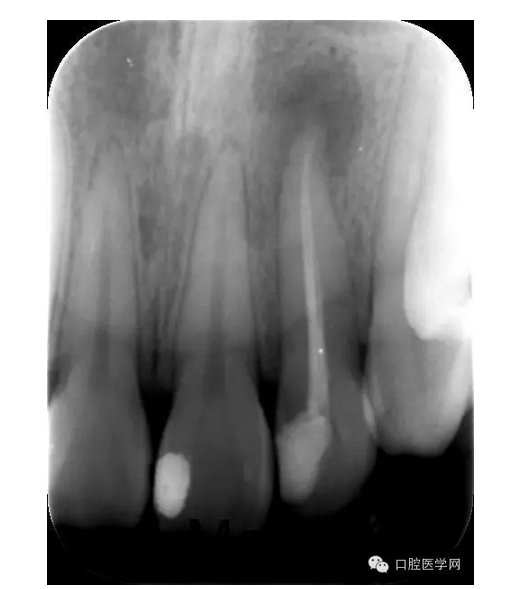

X線片:示22已行根管治療,治療不完善,根尖區(qū)可見約0.5*0.5mm密度減低區(qū),牙周膜影略增寬。